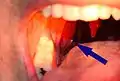

Occasionally there may be pain when swallowing.[8] Even when they are large, some tonsil stones are only discovered incidentally on X-rays or CAT scans. Other symptoms include a metallic taste, throat closing or tightening, coughing fits, and choking.

Larger tonsil stones may cause recurrent bad breath, which frequently accompanies a tonsil infection, sore throat, white debris, a bad taste in the back of the throat, difficulty swallowing, ear ache, and tonsil swelling.[7] A medical study conducted in 2007 found an association between tonsilloliths and bad breath in patients with a certain type of recurrent tonsillitis. Among those with bad breath, 75% of the subjects had tonsilloliths, while only 6% of subjects with normal halitometry values (normal breath) had tonsilloliths. A foreign body sensation may also exist in the back of the throat. The condition may also be an asymptomatic condition, with detection upon palpating a hard intratonsillar or submucosal mass.

A tonsillolith protrudes from the tonsil